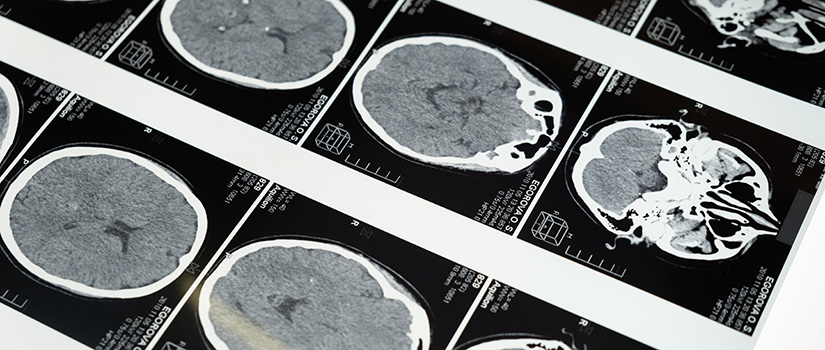

Created to meet the needs of patients and caregivers in rural and underserved areas, the USC Brain Health Network partners with health systems to provide equitable diagnostic and treatment access for individuals seeking cognitive care.

- A Brain Health Center in Columbia will open in 2026 to support patients and clinical providers through innovative research and advanced imaging and treatment options.

HopeHealth will host USC Brain Health’s team-based care model, connecting patients to a nurse practitioner, speech-language pathologist and community health worker to bridge critical gaps in early diagnosis, education and family support.